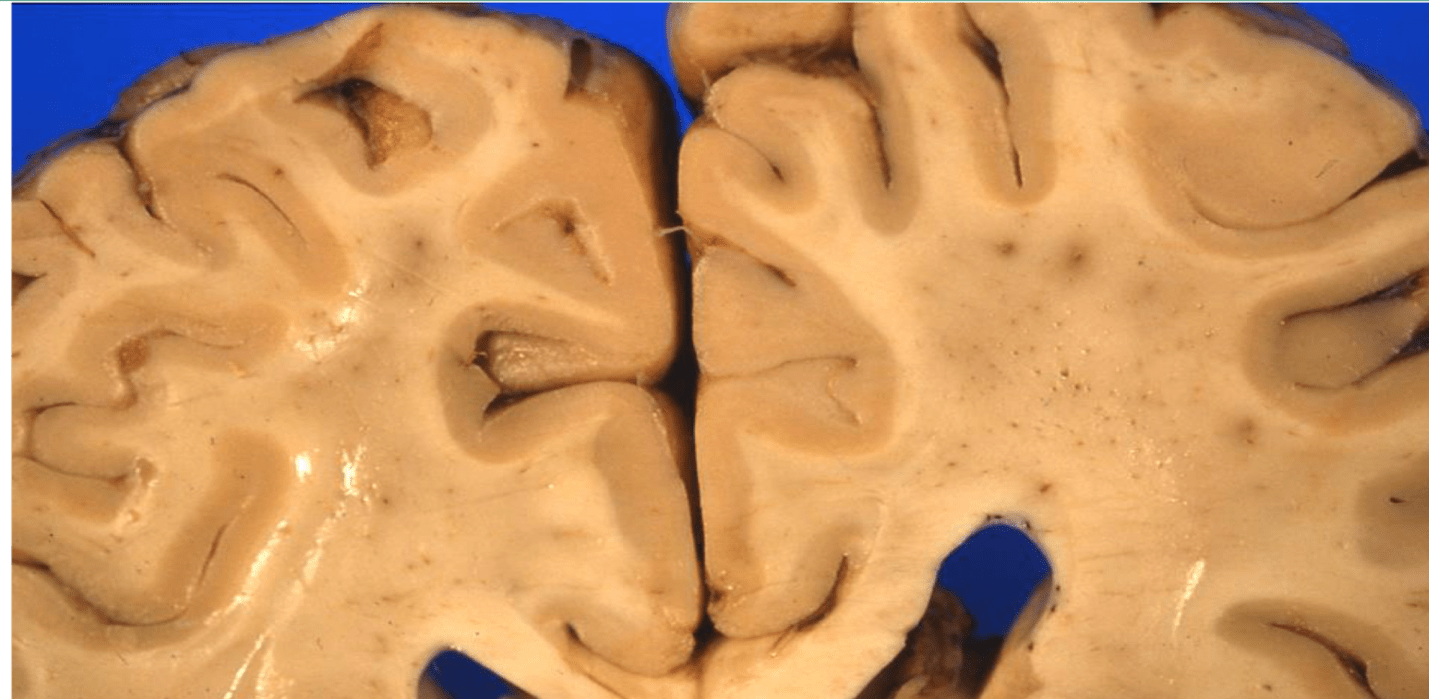

This gross brain specimen would be indicative of what kind of dementia?

What is FTD?

these are the general findings seen with frontotemporal dementia

*younger onset: 50s-60s

*there is a behavioral variant (R frontal)

*primary progressive aphasias (L frontal or L temporal)

*other tauopathies may be present (PSP, CBD)